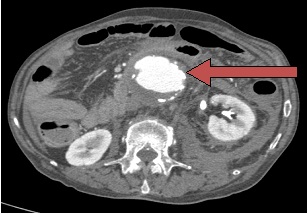

Στην κοιλία δημιουργείται  συνήθως κάτω από τις νεφρικές αρτηρίες όπου διατείνεται η κοιλιακή αορτή κατά 50% και πάνω. Πολλές φορές η διάταση αυτή επεκτείνεται και στις λαγόνιες αρτηρίες που αποτελούν τη συνέχεια της κοιλιακής αορτής προς τα κάτω άκρα. Η ανεύρεση του ανευρύσματος γίνεται συνήθως τυχαία σε έλεγχο της κοιλίας για κάποιο άλλο πρόβλημα με έναν απλό υπέρηχο ή αξονική τομογραφία.

Η εξέταση που θα μας δείξει ακριβώς τις διαστάσεις του ανευρύσματος και την έκτασή του καθώς και τον τρόπο αντιμετώπισής του είναι η αξονική τομογραφία άνω και κάτω κοιλίας με ενδοφλέβια έγχυση σκιαγραφικής ουσίας.